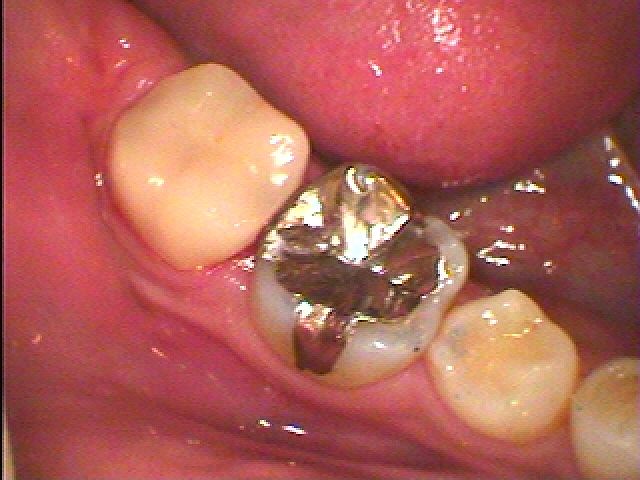

セラミックによる審美治療。 虫歯治療。| |広島市安佐南区の歯科医院 セラミックによる審美治療。 虫歯治療。 トップ お知らせ・ブログ セラミックによる審美治療。 虫歯治療。 セラミックによる審美治療。 虫歯治療。 Web診療予約 初めての方へ 選ばれ続ける理由 院内設備について 歯が痛いしみる一般歯科 歯がぐらぐらする歯周病 健康な歯を保ちたい予防歯科 子供の虫歯予防をしたい小児歯科 銀歯をセラミックに審美歯科 白い歯を目指しませんか?ホワイトニング 矯正専門医がいるので安心矯正歯科 抜けた歯を補いたいインプラント・入れ歯 医院案内 スタッフ紹介 メリィハウス歯科クリニックオフィシャルホームページ ラベンダー歯科クリニックオフィシャルホームページ お知らせ・ブログ ホーム 診療科目 一般歯科 歯周病治療 予防治療 小児歯科 審美治療 ホワイトニング 矯正歯科 入れ歯・インプラント マウスピース矯正 初めての方へ 院長・スタッフ 設備紹介 医院案内・アクセス メニューを閉じる